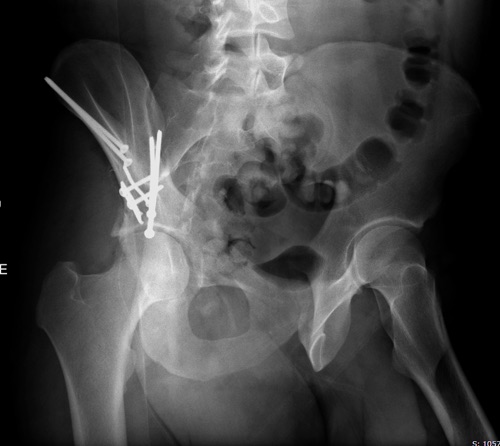

Вместо огромного аппарата, пластина на крыле и винты через AIIS

(anterior inferior iliac spine) из места прикрепления прямой мышцы

создали бы более элегантную фиксацию. Насчет отсутствия материала,

Здесь пример перелома передней стенки, где сохранен принцип фиксации

передней колонны. Для доступа Smith Petersen с остеотомией ASIS. Мышца

сарториус отодвинута, и сделана ре-фиксация на свое место винтами. При

хорошем обзоре, наличие Farabeuf или Jungblud forceps облегчит репозицию.